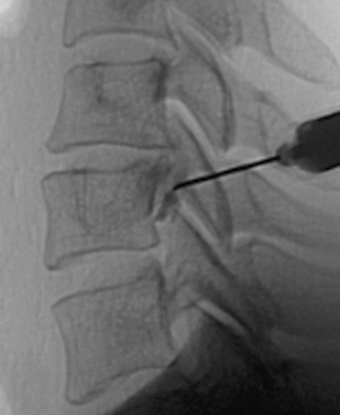

주사 요법, 약물치료

도수치료

체외 충격파 치료